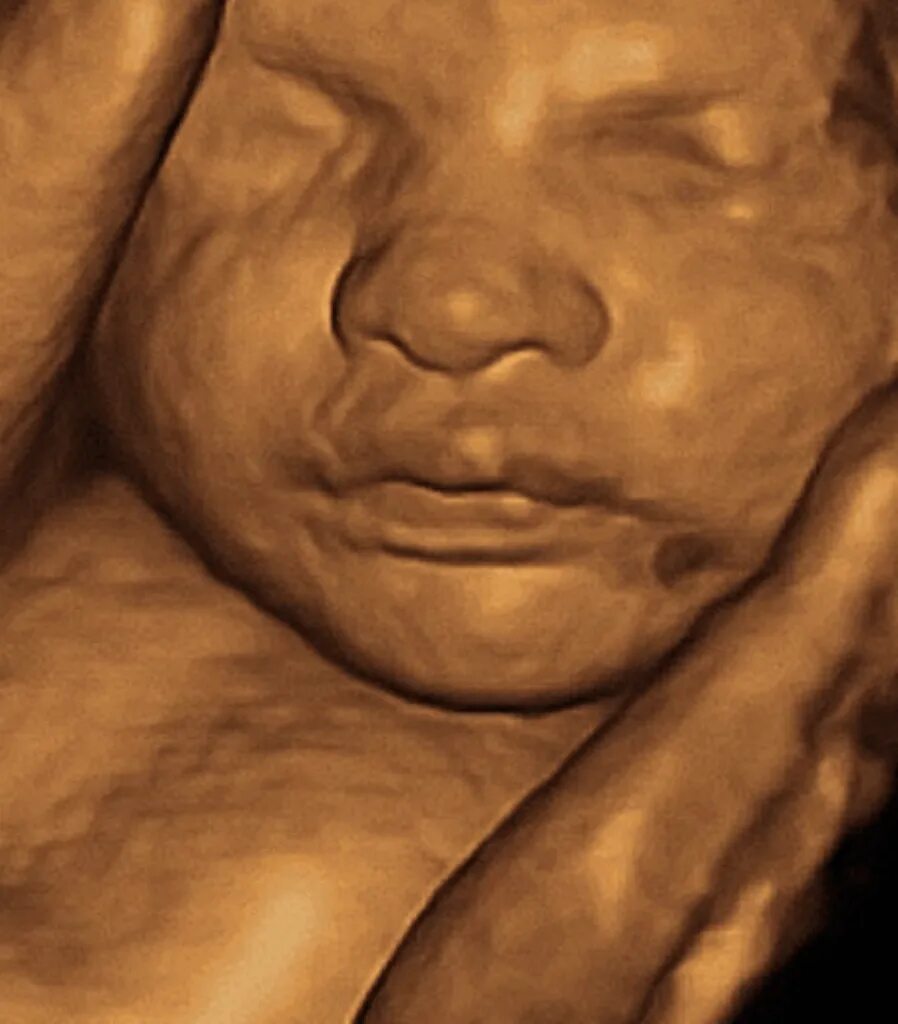

Скрининг 30 недель